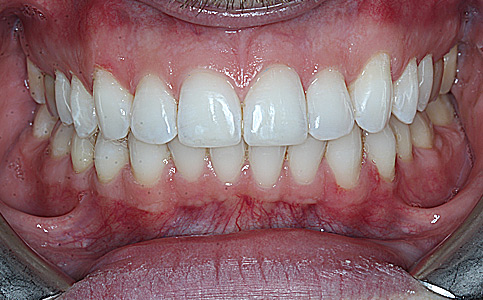

Kompleksowa metamorfoza naszego Pacjenta obejmowała leczenie ortodontyczne nakładkami invisalign oraz korektę zębów przednich BONDINGIEM- estetycznymi odbudowami kompozytowymi. Po zakończonym leczeniu Pacjent jest szczęśliwym posiadaczem pięknego prostego uśmiechu.